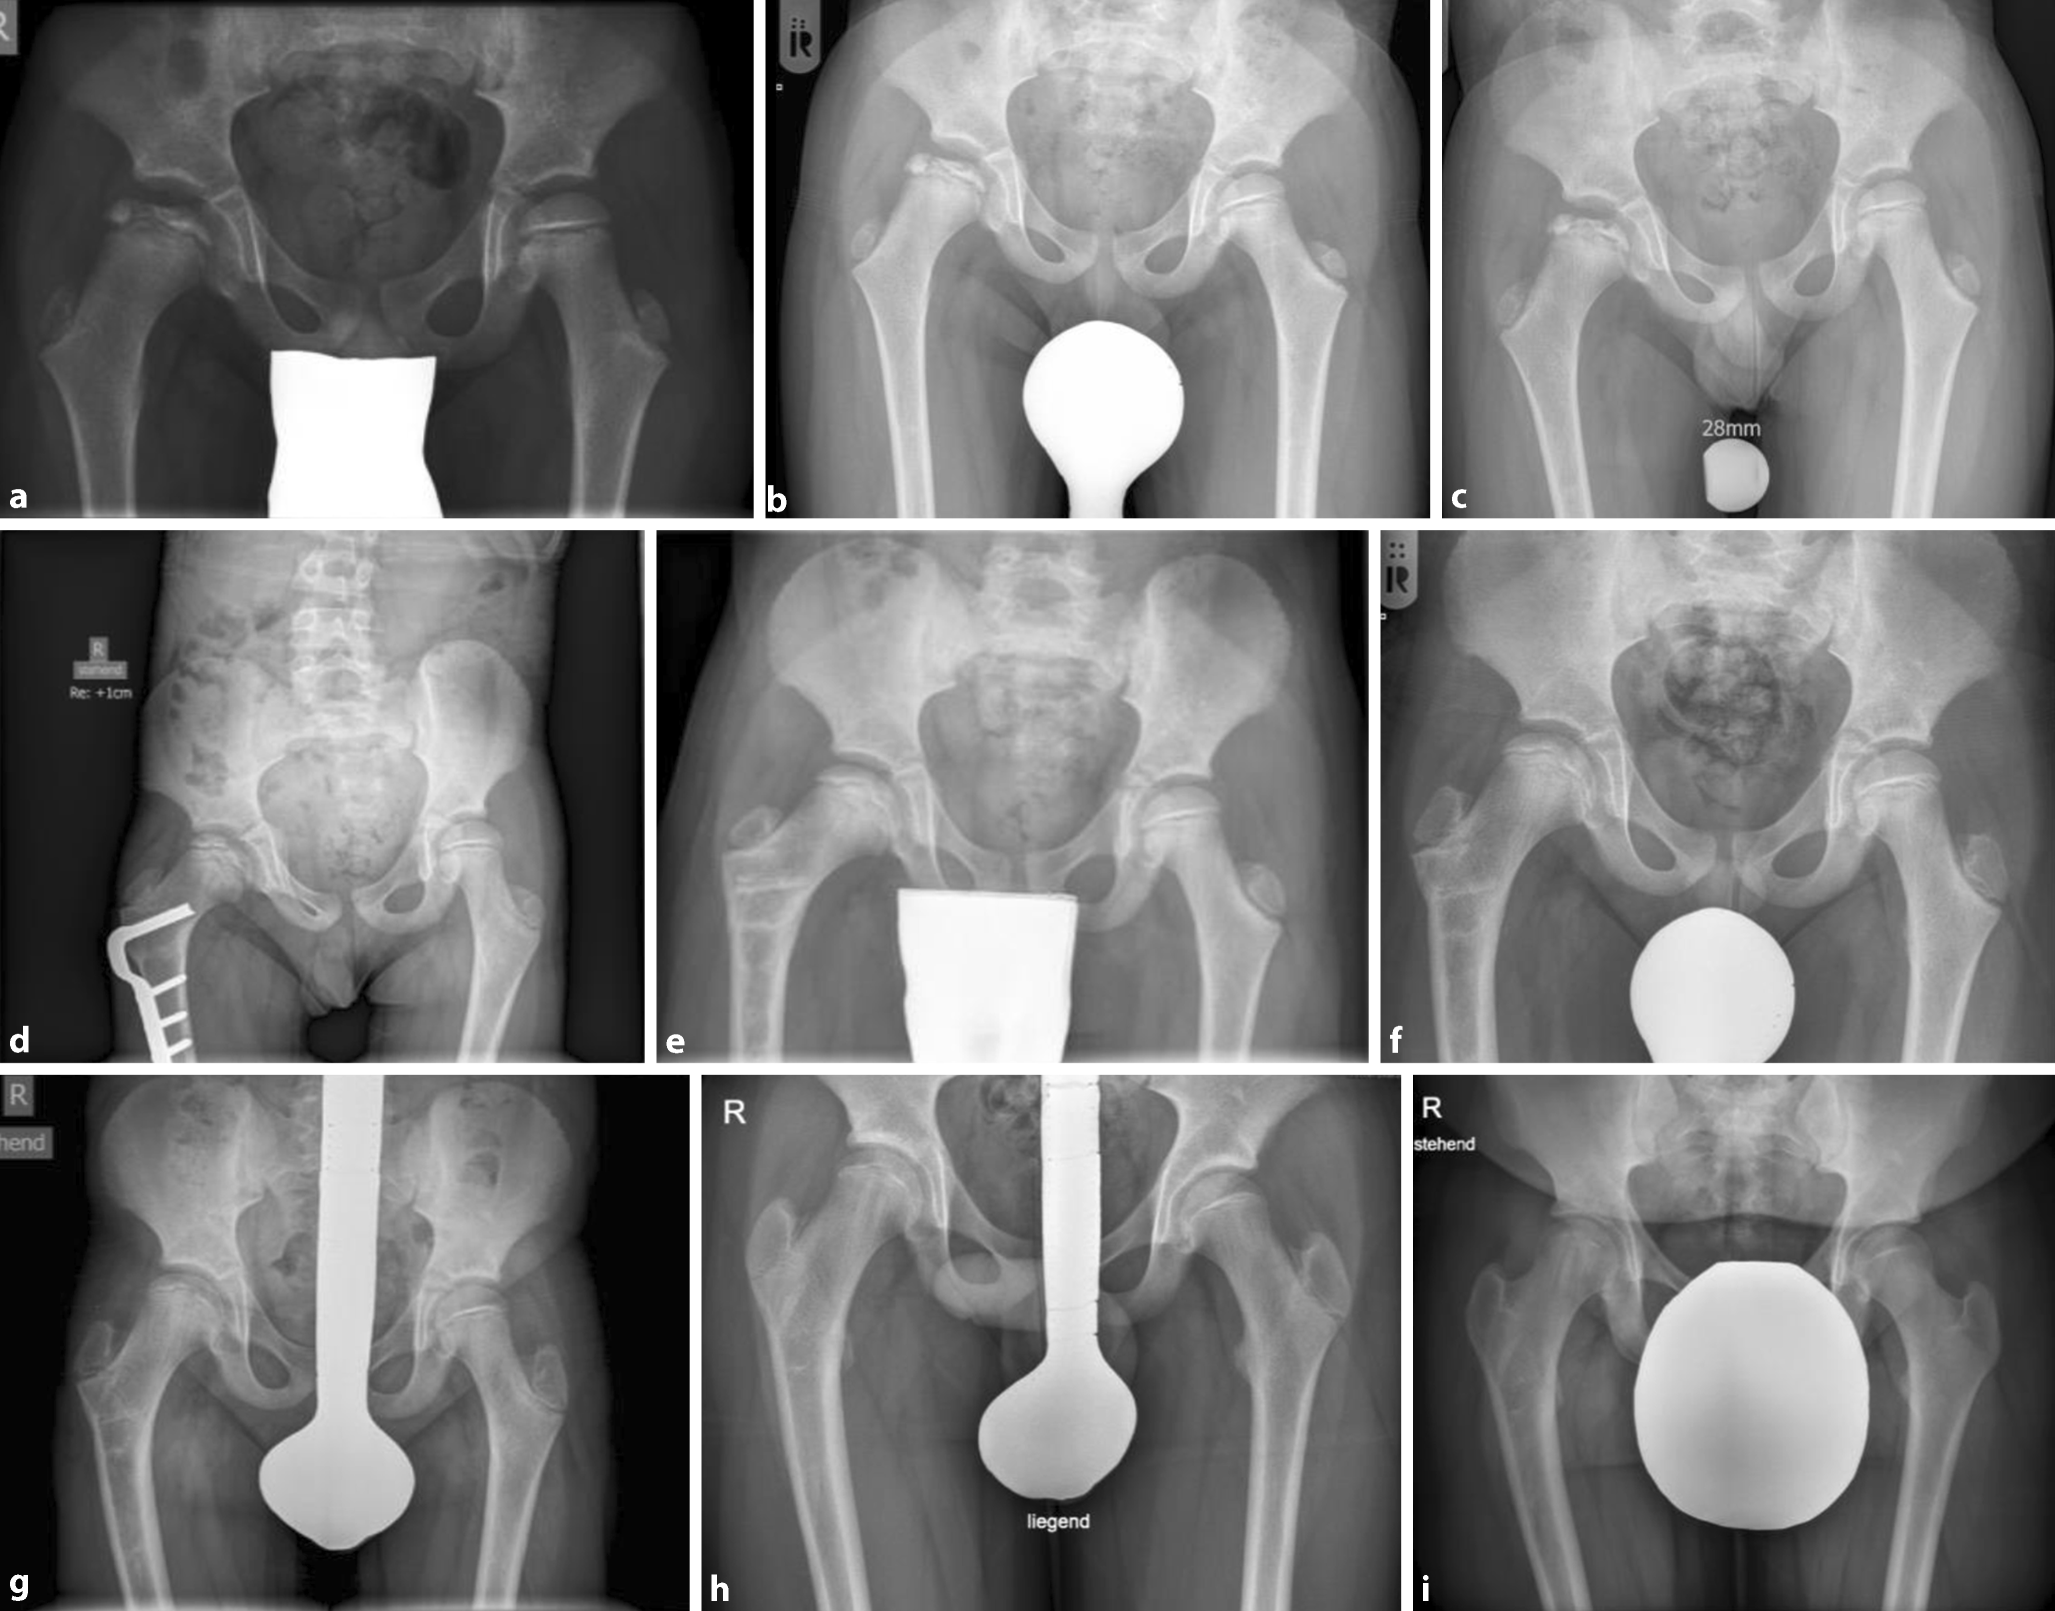

Abb. 2

Vier röntgenmorphologische Krankheitsstadien (horizontal von links nach rechts) und ab dem 3. bzw. Fragmentationsstadium unterschiedliche Verläufe je nach Ausdehnung der Nekrose des lateralen Pfeilers der Femurkopfepiphyse: oben Herring-Typ A, unten Herring-Typ C („lateral pillar classification“). Im Reparationsstadium (vertikal ganz rechts) sind die Ergebnisse nach konservativer Behandlung zu sehen: a Restitutio ad integrum, b Coxa magna/sphärisch und kongruent, c schwere Deformität und d nach operativer Behandlung (sphärisch und kongruent)

Radiologisch kann zur Beurteilung des Schweregrads die Nekrosearealausdehnung im Femurkopf gemessen werden. Diese erfolgt gemäß der Herring-Klassifikation, bei der das Fragmentationsstadium erreicht sein muss, um die Beurteilung zu ermöglichen (Abb. 2). Für die Einteilung in 3 Gruppen wird das Ausmaß der Höhenreduzierung der lateralen Femurkopfepiphysensäule („lateral pillar classification“) beurteilt. Der prädiktive Wert der Herring-Klassifikation erhöht sich bei gleichzeitiger Berücksichtigung des Skelettalters zu Krankheitsbeginn [12, 13, 14]:

Abb. 3

Krankheitsverlauf mit konservativer Therapie bei Morbus Perthes links. a (und d) 3 Jahre, b 4 Jahre, c 5 Jahre